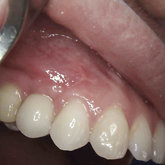

Porcelain crowns and restorations made in one appointment.

We make it a priority to incorporate the latest in dental technology in everything we do at our practice. ...